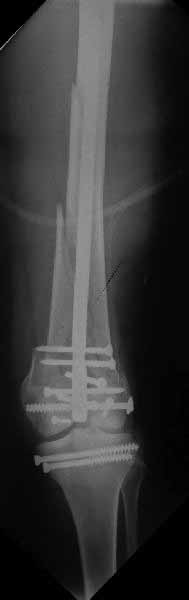

В приложении пример недавней операции, C3, открытая репозиция, фиксация мыщелков спицами и винтами, ретроградный синтез большеберцовым гвоздем 10,5 мм диаметром, винты 5 мм.

Позволю себе напомнить коллегам ещё раз, что являюсь сторонником антеградного остеосинтеза при переломах дистального эпиметафиза бедренной кости. Такая приверженность основана не на преимуществах внесуставного введения стержня или большем проценте положительных результатов. Она основана на возможности обеспечить блокирование на минимальном расстоянии от суставной поверхности в нескомпрометированной кости и, таким образом стабилизировать максимально низкие переломы. В приведенном Вами случае самый дистальный из блокирующих винтов проведен на расстоянии более 2 см от конца стержня. Из-за того, что к стержню присоединяется кондуктор, на стержне теряется 1-1,5 см его длины, где можно было разместить отверстия для блокирования. И что более важно, вместе с потерянной для этой цели длиной стержня утрачивается для размещения блокировочных винтов, пожалуй, самая ценная часть дистального эпиметафиза бедренной кости. Проблемы дистального блокирования в разных плоскостях, локализации точки ввода стержня при антеградном остеосинтезе – это всё решаемые технические проблемы. Но антеградный остеосинтез низких дистальных переломов бедра при адекватном блокировании в нескомпрометированной кости обеспечивает решение стратегической задачи – стабильный остеосинтез и возможность нагрузки.

Но практика показывает, что классификации существуют не зря, и стоит пользоваться ими, а не ориентироваться на абстрактные "максимально низкие переломы". Подавляющее большинство поступающих к нам больных с дистальными переломами - это C1 и С2. И показанный в прошлом сообщении гвоздик прекрасно справляется. Наверно, сгодятся и многие современные гвозди разных производителей, типа RAFN Synthes. А вот при настоящих C3 одним гвоздем не обойтись, нужны как минимум винты мимо, а то и введение на одном уровне нескольких винтов и/или спиц веером...

На этом большеберцовом стержне центр ближайшего к кондуктору отверстия в 14 мм от конца. И пример был про то, что пластина тут, скорее всего, была бы не худшим выбором.